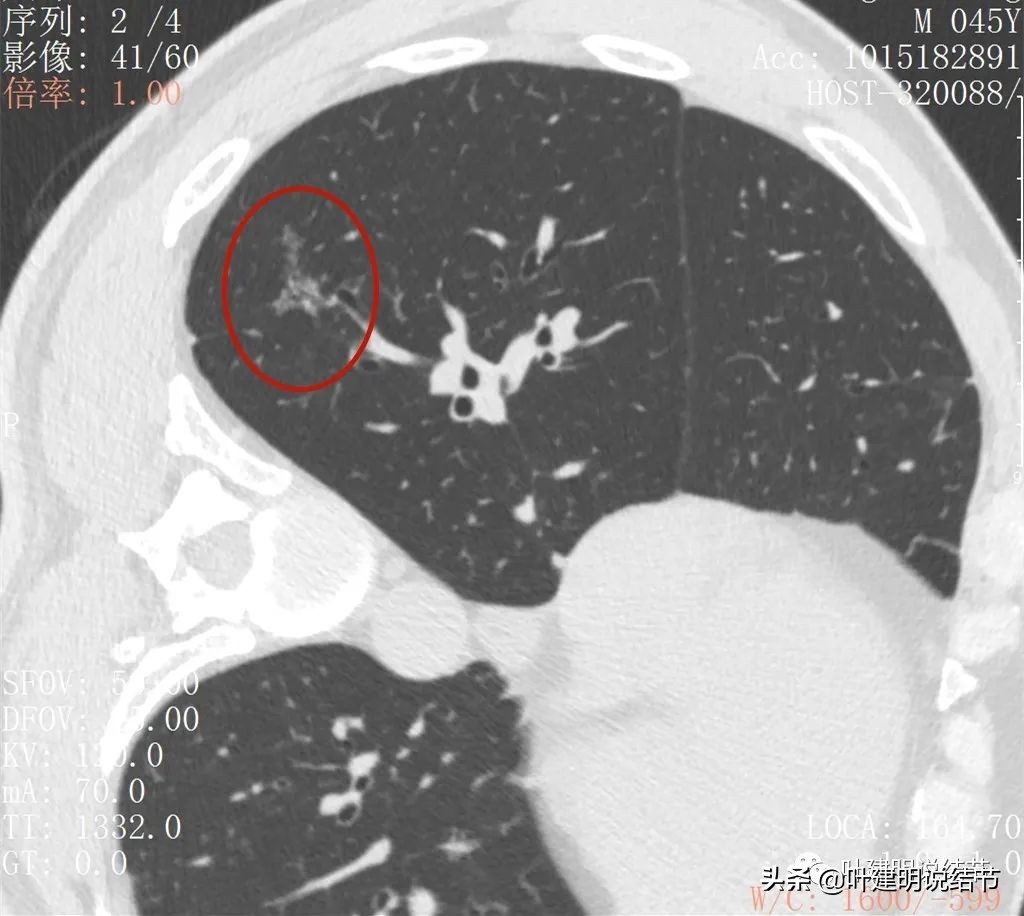

2022年2月平扫:

右下叶淡而散在的磨玻璃影

整体轮廓有点清楚,似见血管走行于病灶处

密度略不均